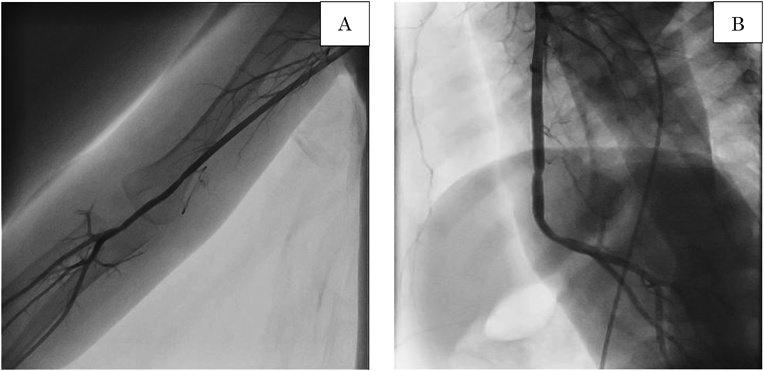

Fig. 6 Follow up angiographic imaging

Angiography shows the graft is patent with no stenosis of the graft in the frontal view (A) or lateral view (B).

In this study, we present a case of idiopathic true brachial artery aneurysm in a 21-month-old infant. The aneurysm was successfully resected and surgically repaired with vein grafting without any complications. Since the 1970s, 16 cases of idiopathic true aneurysm have been reported in children younger than 18 years of age.1, 3–12) In five of these 16 cases, the aneurysm was located in the brachial artery of a patient younger than 2 years of age; surgical treatment was performed in all of these cases.1, 3, 7, 8, 10) Peripheral artery aneurysms are rare in childhood, and only 5% of them occur in the upper extremities.13) Brachial artery aneurysms are usually associated with other traumatic and non-traumatic causes: congenital heart disease, infection, hereditary diseases (e.g., Marfan syndrome, Ehlers-Danlos syndrome, and Turner syndrome), and inflammatory diseases (e.g., Kawasaki disease, Behcet’s disease, Takayasu disease, and giant cell arteritis). However, in our case, there was no history of trauma; congenital heart disease was excluded due to the findings of echocardiography and cardiac catheterization, and hereditary disease was also excluded because of the absence of typical physical findings; inflammatory disease was not considered because the antibody screens for autoimmune diseases were all negative, except for mildly elevated CRP and sIL-2R. Postoperative histopathological examination showed that the wall of aneurysm formed the normal three layers of the artery without any inflammatory cell or polynuclear leukocyte infiltration, fibrinoid denaturation, and granuloma. These results clearly indicate an idiopathic true artery aneurysm (Fig. 5A–D). In general, an asymptomatic brachial artery aneurysm does not necessarily require emergency surgery. It may be better to continue having follow-up observations of small asymptomatic aneurysms in very young children until the child grows larger. However, if aneurysms are of moderate or large size, growing or causing neurologic or vascular symptoms, surgery should be performed. Regarding surgical options, end-to-end anastomosis can be performed after resection in the case of small lesions. For large lesions, reconstruction using a vein graft may be needed.7) We decided to perform surgery despite the young age of the patient because we were concerned about the risk of thromboembolic complications and neuronal disorders secondary to compression by the rapidly growing aneurysm.7) We considered several repair options after resection of the aneurysm and finally decided on end-to-end anastomosis using an autologous vein because of the size and location of the aneurysm. The great saphenous vein is often used as the autologous vein; however, we selected the cephalic vein for the graft in this case. The cephalic vein is the appropriate caliber for the graft and is found more easily than the saphenous vein. Moreover, the wall of the cephalic vein is supple and easier to handle during reconstruction.14) It is still unknown whether the cephalic vein is better suited for the graft than the great saphenous vein; however, we believe it was the better option in this case as we were able to complete the surgery without any additional scars to the lower limbs. We confirmed that the cephalic vein graft worked very well even months after the operation, as demonstrated by the follow-up angiographic imaging.